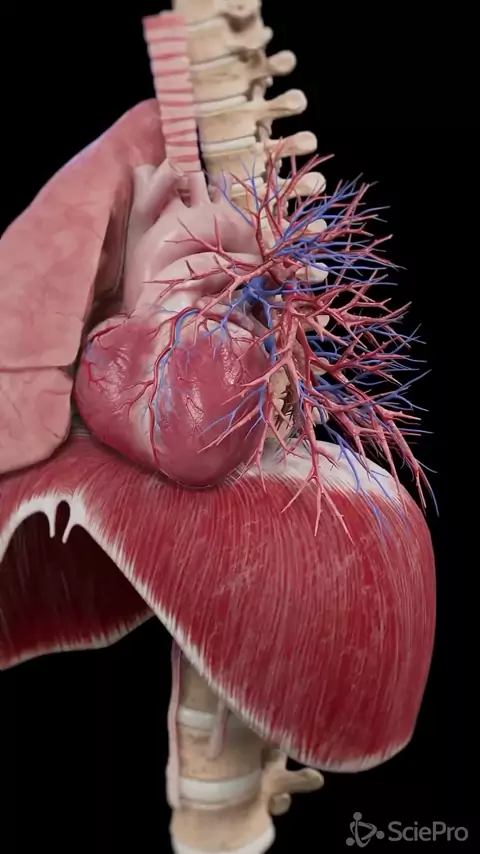

Rafael Gonçalves

A anatomia humana é realmente fascinante! O corpo humano é uma estrutura complexa e altamente organizada, composta por sistemas que trabalham em perfeita harmonia para manter a vida. #anatomia #fisiologia #estudos